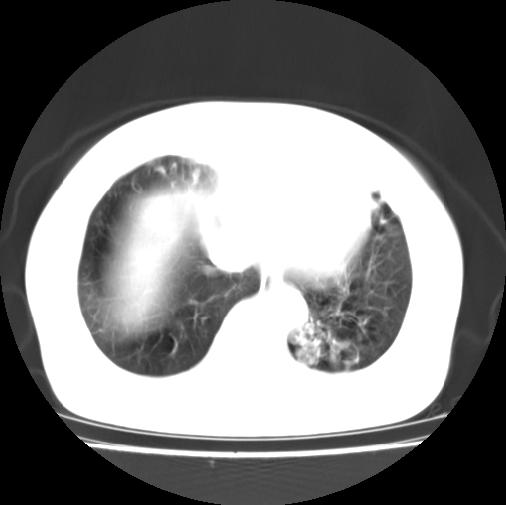

女性病人,56岁,反复咳喘30余年,伴大量脓痰,偶有痰中带血。

此病例在科室里有较大的争议,我认为是先天性肺囊肿(理由是:两者起病年龄都较轻,都有咯血及脓痰的症状,而先天性肺囊肿壁薄;而支扩的囊腔旁一般都能看到伴行的血管影,形成“印戒”征)。以上为个人的意见,请高手们指点一下。

本例应为支气管扩张并感染,与囊肿区别在于其大小,分布,壁改变,与肺动脉关系,形态等来鉴别,要点大家都说得差不多了,囊肿要大些,分散些,靠外围一些,而支扩靠内一些,聚拢些,小一些且易聚拢呈葡萄状,不能单从囊壁厚度来评价,特别是有粘液栓类的改变更加支持支扩,有时支扩亦与囊肿混在一起并存.个人意见仅供参考.